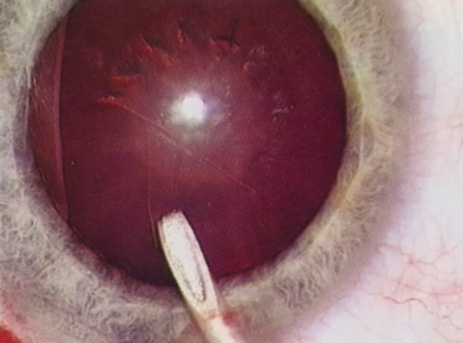

further tests guide the ophthalmologist in planning the surgery. SPECIAL MEASUREMENTS OF VISION Preoperative measurement of vision is meant to determine the patient's current state of visual function. Snellen acuity is routinely tested on all patients as part of their preoperative evaluation. This usually is performed by having the patient read a standardized chart in a darkened room. Although the Snellen acuity scale is the most ubiquitous measure of vision, it measures only one tiny aspect of visual function. Many patients may be profoundly functionally impaired by their degree of visual disability, yet may test surprisingly well measuring Snellen acuity in a darkened room. In these cases, it is incumbent on the ophthalmologist to seek to better understand and document the patient's problems by performing additional testing. Many patients are most bothered by cataract-induced glare. For these patients, acuity testing under glare situations is indicated. There are several methods to assess visual acuity reduction by glare. The choice of method is often best dictated by the patient's history. If a patient complains of glare problems in the supermarket, or other uniformly illuminated environment, the brightness acuity test can be performed (Mentor Ophthalmics). For this test, the specially illuminated handpiece is held in front of the tested eye using best spectacle correction (Fig. 1). The Snellen acuity is rechecked and can be recorded on each of three light settings. Patients who complain of glare from point sources of light, such as oncoming headlights or bright sunshine, may be best evaluated by a different form of glare testing. To simulate the environment of the patients' symptoms, Snellen acuity is measured while directing a point source of light obliquely toward the eye outside their best spectacle correction or outside of a phoropter dialed in with their best manifest refraction (Fig. 2). Still other patients' problems may center on difficulty with reading, seeing street signs, or distinguishing fine patterns. In these individuals, the complaints are related more to contrast; therefore, contrast testing is most appropriate. There are a number of ways to assess the effect of contrast on vision. Regan's sine wave gradients have been used frequently for research purposes and are available in some settings. Various commercial devices are now available to measure visual acuity in different contrast settings and each has its relative merits and detractions. The authors have found the Baylor Visual Acuity Tester (BVAT) monitor (Mentor Ophthalmics) testing of contrast to correlate well with patients' complaints and its simplicity is appealing to both patients and technical staff. In rare instances, patients' complaints may be primarily related to distinguishing colors. Although patients frequently remark about their dramatic improvement in color perception after cataract surgery, there are no convenient methods to document diminished color perception preoperatively. This underscores the importance of correlating patients' complaints with the biomicroscopic examination and the degree of nuclear color change. PROGNOSTIC TESTS Physicians often order special tests to help determine a patient's visual potential. Some of these tests are acuity specific. These can be particularly helpful in guiding patients who may have comorbid ocular conditions. Some devices have been designed to project a Snellen chart through the clearest area of the cataractous lens to assess retinal acuity potential such as the potential acuity meter. Studies also have shown a good predictive value by checking vision with a brightly illuminated near card.53 Of course, this can be performed with no additional office equipment. Various other commercial devices, including interferometry and various different pinhole and illumination device combinations, are available. These approaches are not possible for patients with mature cataracts. Some more general, nonspecific prognostic tests can be performed. If a patient is able to identify the colors of projected lights, this usually indicates that some cone-mediated macular function is present. Blue field endoscopy also may indicate some macular function. This test is performed by projecting a blue light into the eye. The patient may report seeing small round specks moving around in the vision. These specks correspond to white blood cells passing through the perifoveal capillaries. The Purkinje phenomenon is tested easily by rapidly wiggling a transilluminator directed toward the globe through the lower lid in a darkened room. If the patient reports a pattern of crooked lines or branches, then he or she is seeing the shadows cast by the retinal blood vessels, indicating that the posterior pole is attached and functioning to at least some degree. Although positive results from the test are encouraging, some patients may still have limited vision after surgery; similarly, some rare patients may test negatively on all these tests and still recover good vision. Diagnostic Studies Several diagnostic studies provide information that supplements the historical and clinical data obtained by the surgeon. This information enables proper preoperative patient consultation and surgical planning. This section outlines many preoperative tests used for cataract patients. A-SCAN BIOMETRY. Accurate axial length measurement is critical to determine the correct power of the implant lens for the desired refractive result. A-scan biometry is imperative in any patient undergoing cataract surgery. Both contact (applanation) and immersion varieties of A-scan ultrasound units are commercially available. With applanation biometry, a hand-held or slit-lamp mounted probe is gently touched to the corneal surface along the visual axis. Contact A-scans are user dependent and sometimes the authors adjust the surgeon-specific IOL A-constant depending on which ultrasonographer has performed the scan. Nonetheless, outstanding refractive outcomes have been achieved, and the authors have been satisfied with the contact applanation technique. With an immersion probe, a water bath around the eye acts as the medium to conduct sound waves. Although there is no direct contact of the probe with the globe, the water and water bath must, of course, remain in contact with the ocular surface and periorbita. Immersion scans may reduce interobserver variations but are less comfortable and less convenient for patients. A-scan biometry is particularly challenging in eyes containing an oil fill. In this instance laser biometry is still able to achieve excellent measures. LASER PARTIAL COHERENCE OPTICAL BIOMETRY. Although ultrasound requires continuous contact with media that conduct sound waves, laser light passes easily through any clear media, including air, making this a truly noncontact or “no touch” test. Furthermore, the speed of light is not appreciably different in the clear media of the eye and thus excellent, reliable measures can be achieved in eyes containing intraocular lenses, regardless of type and eyes with oil fills within the vitreous cavity. Although some calculation adjustments can be made depending on the pseudophakic status, the differences among implant material are not appreciable different from a practical clinical perspective. Currently, the only commercially available laser biometry device is the IOLMaster (Zeiss). The measurements obtained by the IOLMaster device are extremely reliable, reproducible, and seem to be relatively technician- and observer-independent.54,55This device also can measure keratometry, optical anterior chamber depth measurements, and “white-to-white” measurements in an automated fashion. Because it relies on the passage of laser light through the ocular media, this instrument is unable to obtain measurements in cases where the media prevent laser light passage; for example, white cataracts, axial posterior subcapsular cataracts, or corneal scarring. B-SCAN ULTRASOUND. A mature cataract precludes visualization of the fundus. A B-scan ultrasonographic examination provides a real-time, two-dimensional (2D), cross-sectional image of the globe along the marked axis of the probe (Fig. 3). Cataracts are more common in patients with chronic retinal detachment, prior trauma, or intraocular tumors; therefore, a B-scan study is helpful in excluding structural posterior segment pathology before surgery on a mature cataract. Although a negative result to B-scan evaluation is reassuring, the surgeon should remember that it does not predict postoperative visual outcome. The B-scan can be thought of as a picture of Cincinnati from an airplane; the office buildings may all be standing, but you cannot tell whether the people in them are working.